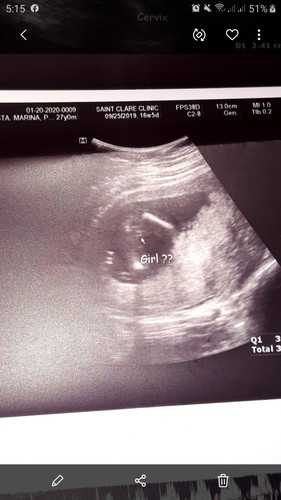

16weeks 4days Pelvic Ultrasound(BabyGirl??)

Sa 16weeks po ba or 4months.. possible ba makita na ang sure Gender ni Baby.. Sabi ni OB me hiwa daw,most likely babae daw dalawa beses nya sinipat. Pero masyado padaw maaga. Excited kasi po ako sa Baby Girl at Boy kasi ang panganay ko tapus 9years old na kasi.?